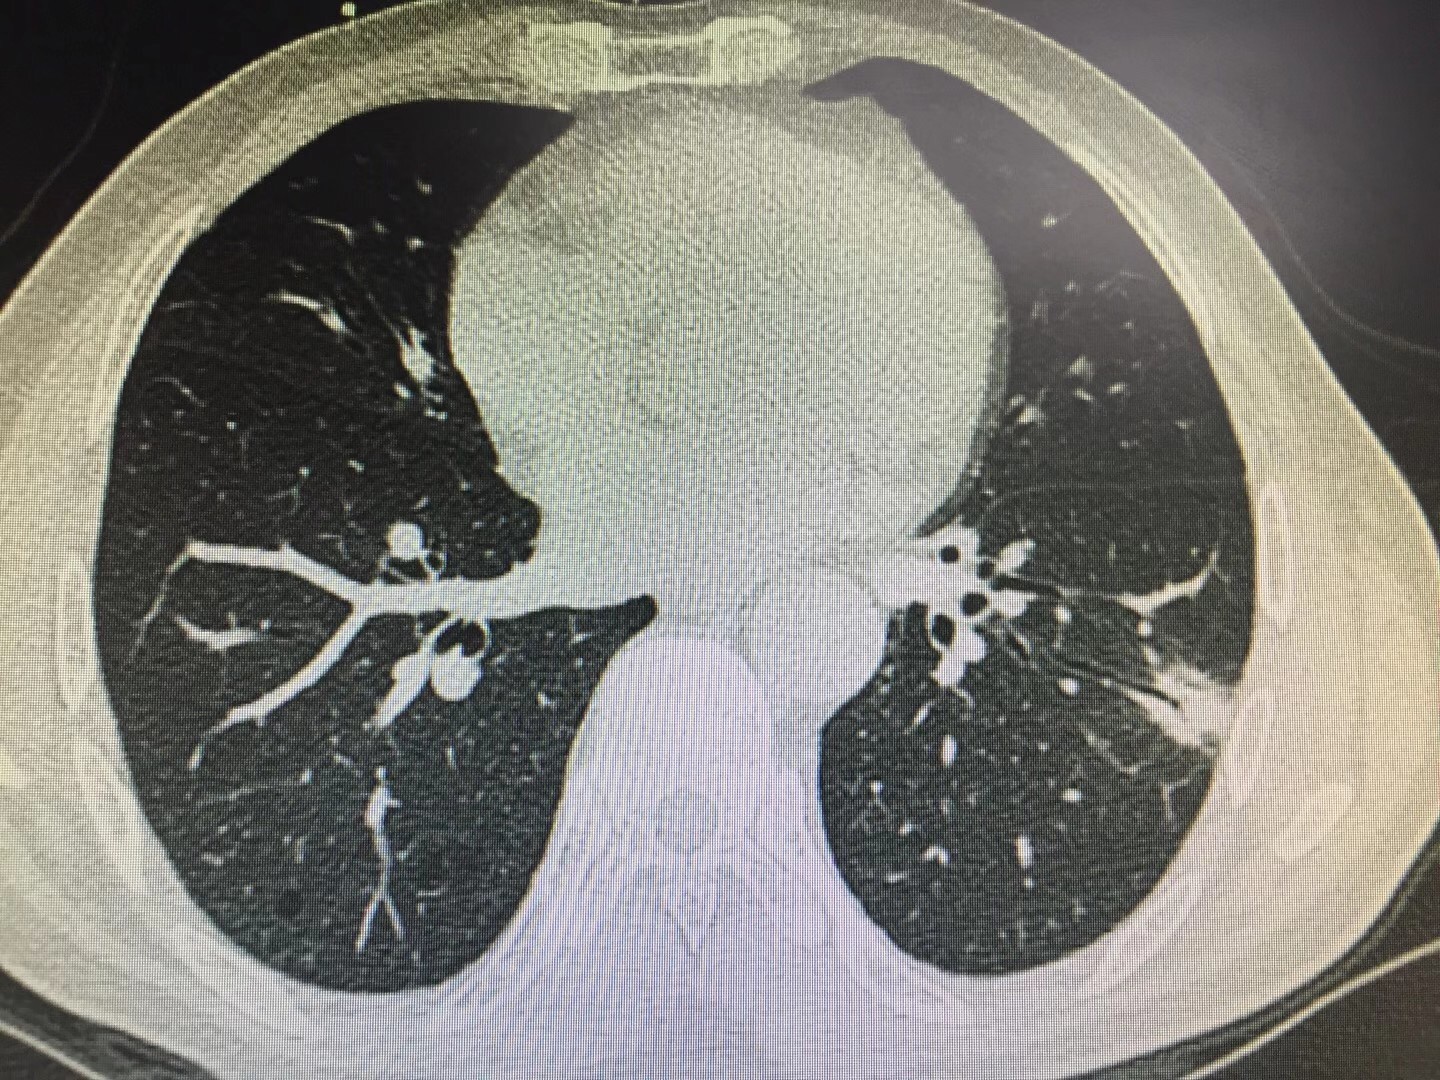

近日,桂林市民蒋先生在体检时发现有肺部占位,在多处求医无果的情况下,慕名到自治区南溪山医院救治,该院呼吸与危重症医学科副主任屈东明为蒋先生会诊时为他详细分析了胸部CT,初步诊断他很可能是肺部隐球菌感染,再对他进行针对性检查后果然确诊为肺隐球菌病。住院期间,蒋先生进行了药物治疗和注射液治疗,在病房医护人员细心照顾下,蒋先生很快康复出院了。

据屈东明副主任介绍,肺隐球菌病为新型隐球菌感染引起的内脏真菌病,主要侵犯肺和中枢神经系统,但也可以侵犯骨骼、皮肤、黏膜和其他脏器。感染后仅会引起轻度炎症反应。肺部有局限性或广泛性肉芽肿形成,坏死和空洞少见。本菌通常经呼吸道进入人体。感染的首发部位是肺。约1/3的患者感染时无任何症状,常在体检中被发现,有时误诊为肺癌。多数患者有轻度咳嗽、咳少量黏液痰或血痰、胸痛、低热、乏力及体重减轻等症状。特别需要注意的是,肺隐球菌病并发脑脊髓膜炎时,则症状明显而严重,脑隐球菌病感染后死亡率高达80%。

图2患者肺部CT照